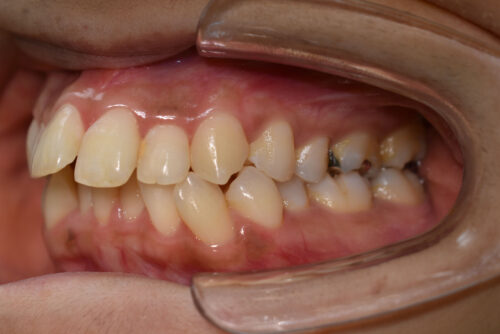

奥歯のかみ合わせに 前後的な ずれは ないものの

上下ともに 前歯部に

顕著な 叢生(でこぼこ)が

認められました。

2026年(令和8年) 春頃 JR巣鴨駅徒歩4分の場所へ 移転予定の

豊島区の矯正歯科専門クリニック 大塚たまみ矯正歯科で

矯正専門の 精密検査を行い

非抜歯矯正治療計画で

矯正治療を開始しました。